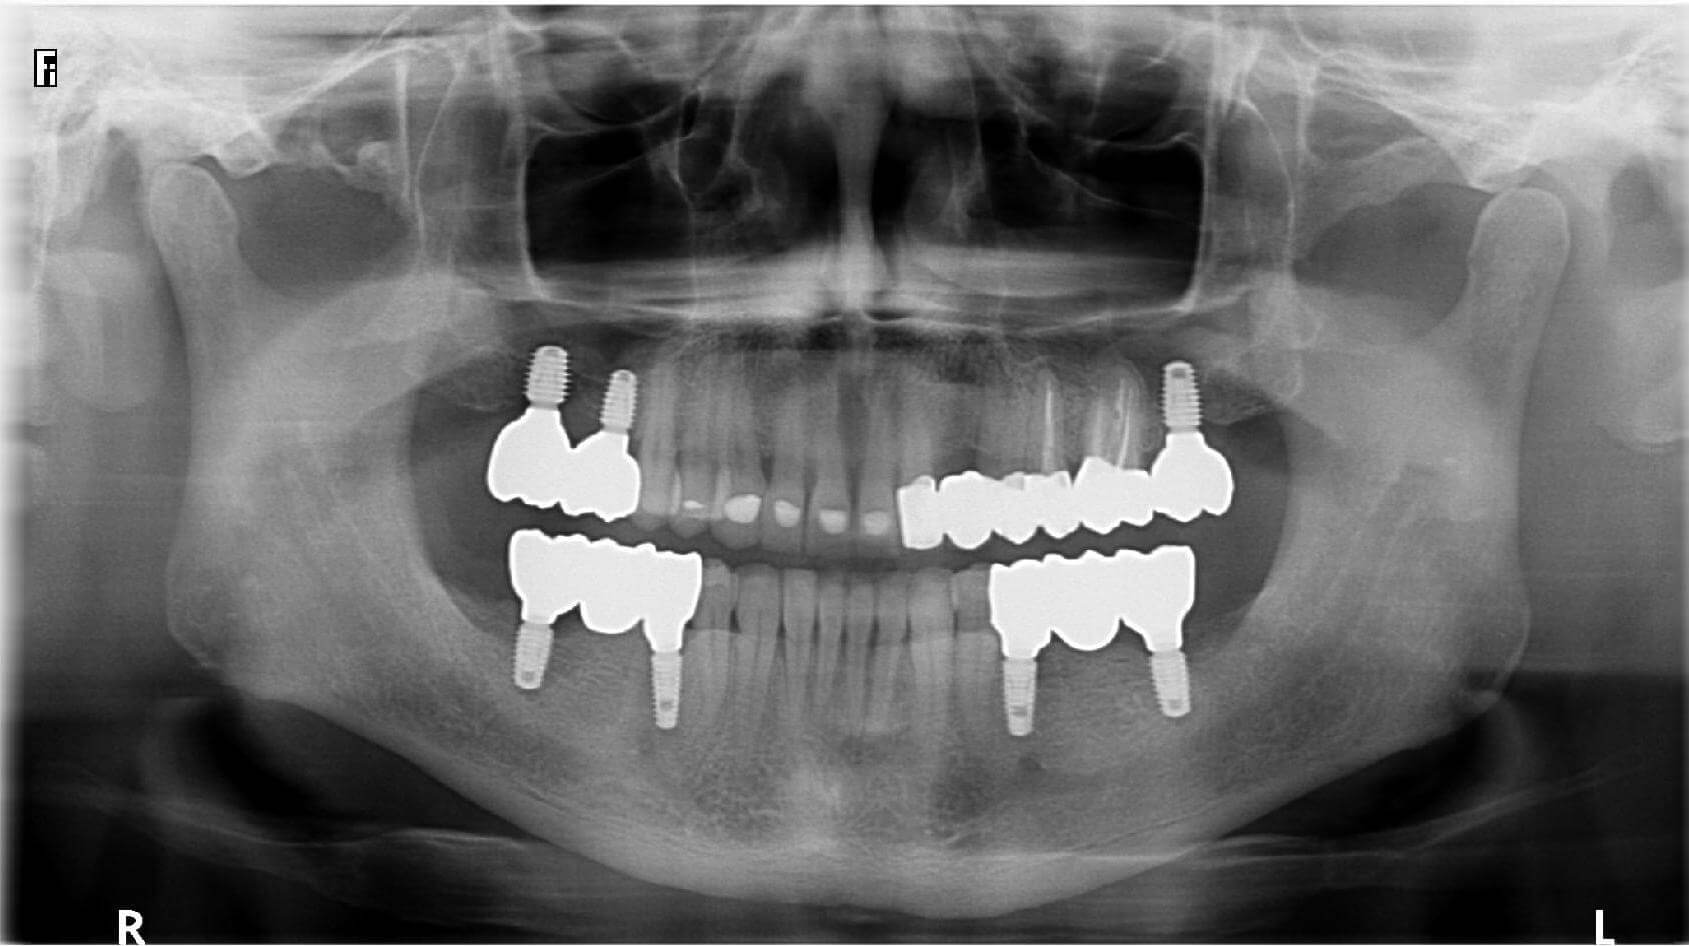

A male patient came to us with complaints of severe wear of the front teeth and the absence of posterior teeth in both jaws. He initially sent us X-rays and photos of his teeth remotely, which allowed us to create a detailed, personalized treatment plan that we later carried out.

At the first visit, the remaining tooth roots were removed, and implants were placed in the posterior areas where teeth were missing. After that, soft tissue grafting was performed in the necessary sites.